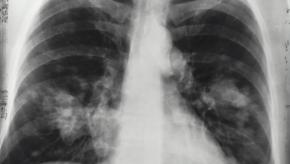

Interstitial Lung Disease and Lung Cancer Risk

A large prospective cohort study found that interstitial lung disease (ILD) is associated with an increased risk of lung cancer.